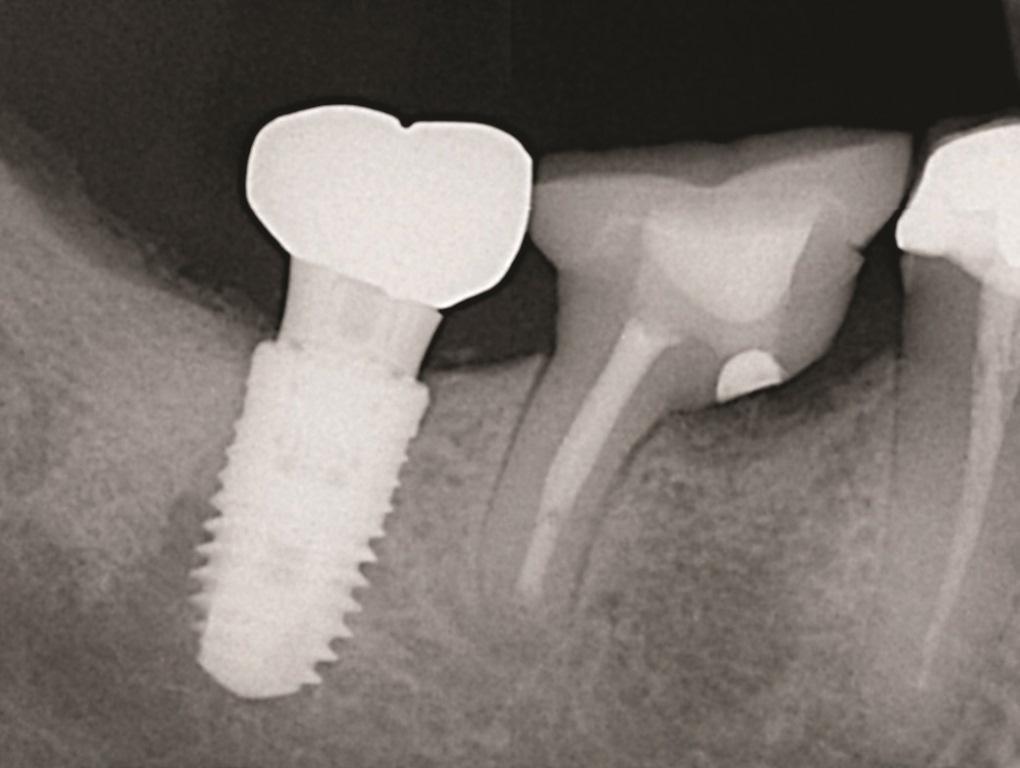

Хотя трансплантат можно разместить в лунке на уровне консольной части зуба, клинические наблюдения авторов показывают, что со временем уровень краевой кости обычно стабилизируется на 1-3 мм ниже консольного участка (Фото 9 и Фото 10). Окончательный уровень восстановленной кости зависит главным образом от способности пациента контролировать зубной налет, что напрямую связано с качеством контурирования при резекции. Это подчеркивает важность тщательного выполнения резекции и формирования правильного контура во время процедуры.

Фото 9: Хотя трансплантат можно разместить в лунке на уровне консольной части зуба (Фото 9), со временем уровень краевой кости стабилизируется на 1-3 мм ниже этого участка (Фото 10).